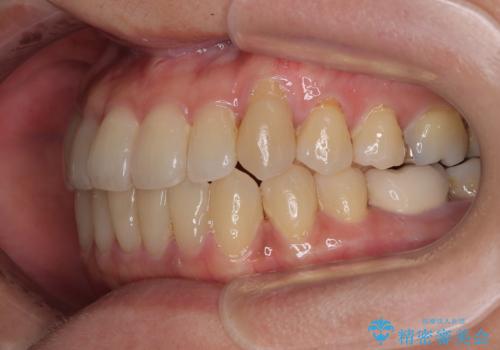

- 前歯のデコボコや八重歯を治したいとのことで来院された患者様です。

受け口傾向の骨格であり、前歯はクロスバイトまたは切端咬合となっており、下顎を中心に歯列全体の後方移動を行い、IPR(歯と歯の間を削る)によってデコボコが解消するように設計し、インビザラインにより治療を行うこととしました。

受け口傾向のインビザライン矯正は比較的治療を行いやすいため、きれいに仕上げることができました。舌の突出癖が顕著であったため、改善のためのトレーニングをしっかりと行っていただきました。